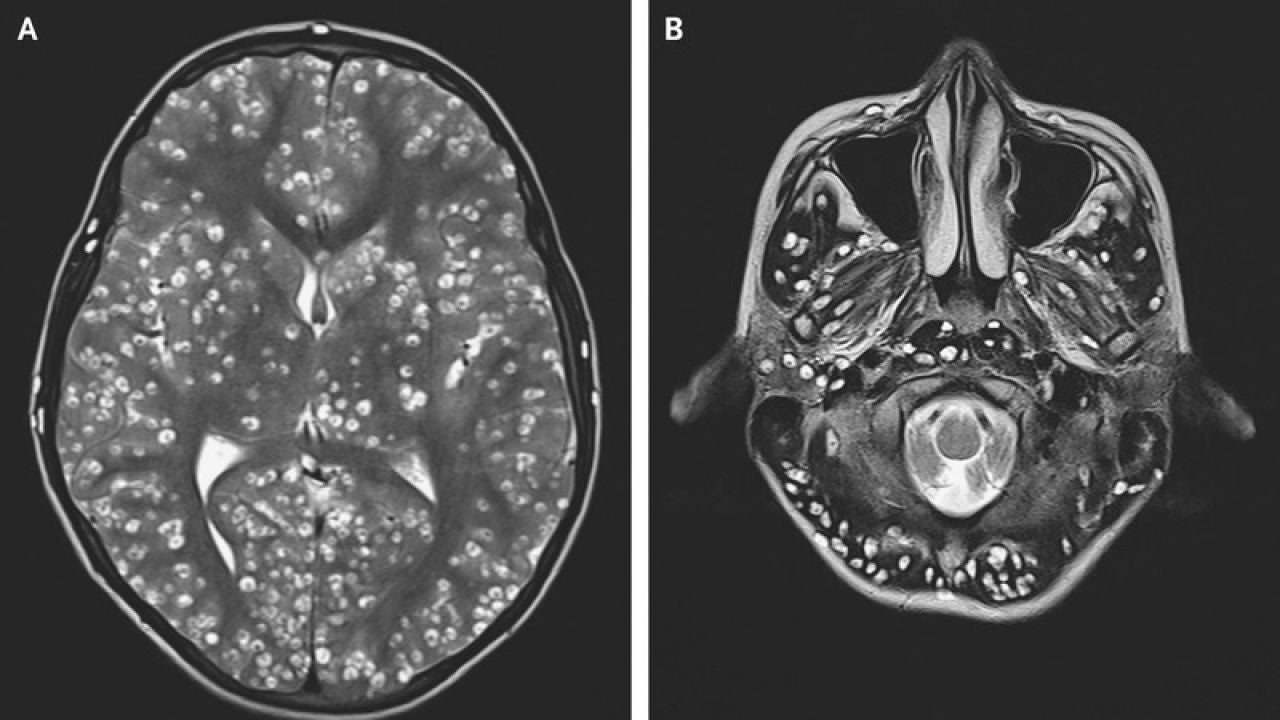

Cerebro del joven infectado con gusanosNew England Journal of Medicine

La joven se sometió a una operación para extirpar el tumor. Durante la cirugía el neurocirujano vio "una lesión bien encapsulada y firme que era ovoide". "Parecía un huevo de codorniz", afirma Rasouli. En ese momento el médico descubrió que no se trataba de un tumor cerebral. El doctor cogió una muestra de la lesión extraída, la colocó bajo un microscopio quirúrgico y descubrió que lo que tenía era una tenia de cerdo.